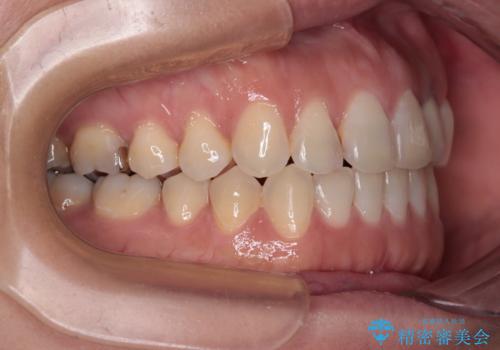

開咬と変色した前歯 インビザライン矯正とオールセラミッククラウン治療

- 前歯の開咬と失活により変色した前歯を気にして来院された患者様です。

開咬の治療は、前歯を閉じるように引っ張り出すよりも、上下臼歯を圧下(骨内にめり込ませる)させることで進める方が長期的に安定した歯列を維持できます。

インビザラインは臼歯の圧下を効果的に行えるため、インビザラインを用いて矯正治療を行うこととしました。

矯正治療が概ね終了した時点で前歯をオールセラミッククラウンにて補綴治療を行い、その後インビザラインにて細かい部分を仕上げていくことしました。